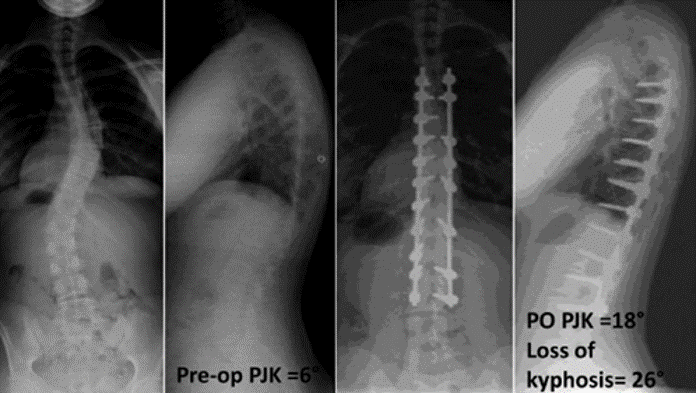

图7 术前-术后1个月-术后1个月外观

(8)脊柱矫形的程度

1) 矢状面失平衡(High SVA)过度矫正

术前-术后SVA矫正过大(大于5cm)的患者,PJK发生的风险增高

矫形术后矢状面失平衡可增加固定融合近端和远端交界区的应力,增加PJK风险

图16 矢状面失平衡过度矫正

图17 据文献报道,腰椎前凸(LL)过度矫正和SVA基线位置不当,均为增加PJK发生的风险因素